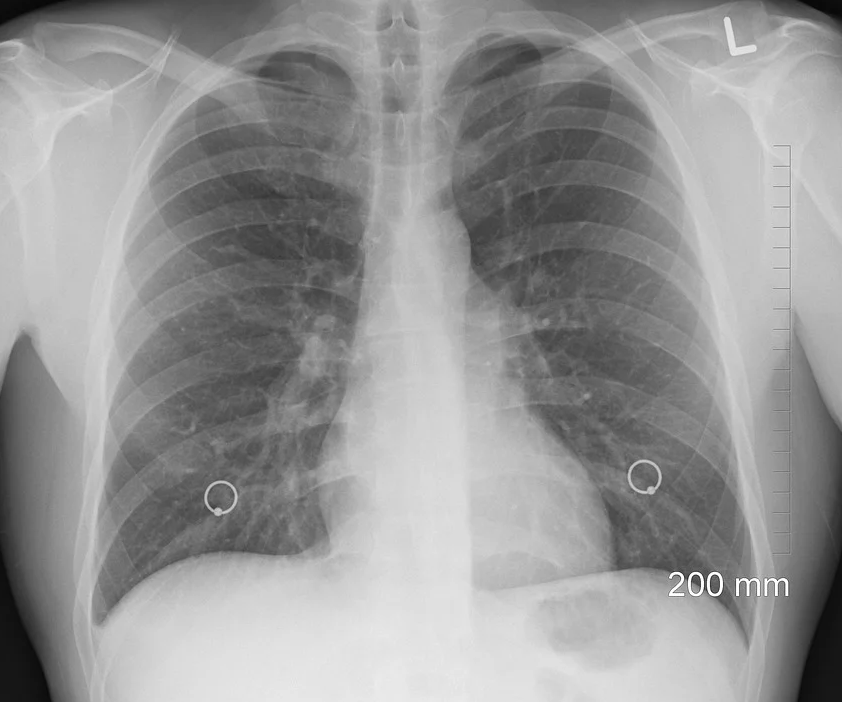

폐섬유증이란?

폐가 바위나 돌처럼 딱딱하게 굳어지는 질병이라고 할 수 있다.

폐 섬유증의 원인은 우리 몸에서 폐포를 성장시키고 폐를 잘 유지시키는 줄기세포인 이형세포의 손상에 의해 혹은 이형세포의 손상에 의해 폐를 부드럽게 만들어주는 표면활성제와 같은 물질이 분비가 잘 안되면 폐가 딱딱하게 굳어지는 것이 그 원인이다.

폐섬유증 증상

증상은 호흡곤란인 경우가 대부분이다. 처음에는 서서히 호흡곤란이 발생하게 되고, 다음에는 마른기침과 같은 것들이 나타날 수 있다.

사실 증상은 특이성이 부족하기 때문에 단순히 '증상'만을 가지고 다른 폐질환과 폐섬유증을 구분하기란 매우 어렵다.

폐섬유증 치료방법

폐섬유증은 완전히 사라지게 하기는 어려운 질병이라고 한다.

그래서 폐섬유증을 늦추는 방법으로 치료를 하고 있는데 크게 적용하는 두 종류의 약재가 현재 사용중이라고 하며, 피르페리돈과 닌테다닙이라는 약재가 사용중이며 전문의와 상의해서 치료하면서 처방받을 수 있는 약재라고 한다.

이 약재들은 폐섬유화를 낮추면서 급성악화나 장기적으로는 생존율에 대한 개선효과까지도 있다고 알려져있다.